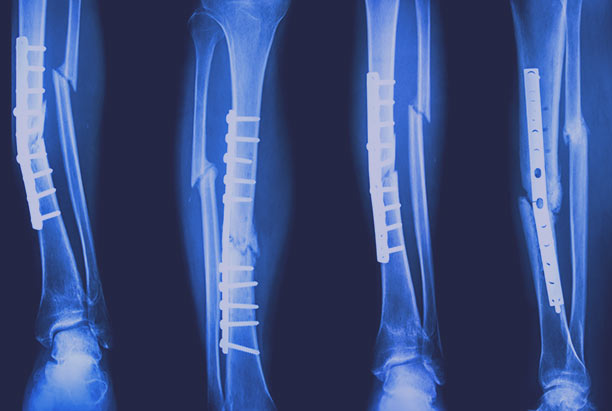

Медицинские снимки: Пластина в левом предплечье